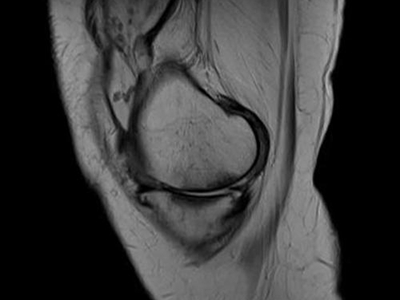

膝关节创伤性滑膜炎是指膝关节外伤后发生的膝关节滑膜无菌性炎症反应,急性损伤性膝关节滑膜炎,可发生于任何年龄。本病以关节疼痛、肿胀为主要临床表现。

膝关节创伤性滑膜炎可表现为局部胀痛,在膝关节完全伸直或属曲时胀痛感更明显,此外,由于局部淤血,可导致局部出现青紫色。局部可逐渐出现关节肿胀,并伴有活动受限、压痛等症状。